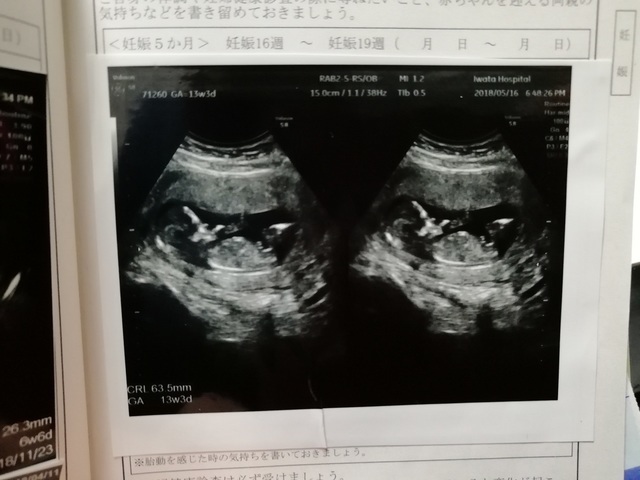

13週1日(13w1d・女の子)|y twin mam さん(36歳)

エコー写真撮影時のエピソード:

画像は悪いですが、双子ちゃんが一緒に写った貴重なエコー写真です♪ この頃はつわりがあり、出血もありで、仕事をしながら不安な日々を過ごしてました。

今は34週に入りましたが、赤ちゃんたちはずっと問題なくすくすくと育ってくれています。 待望の赤ちゃんたち。無事に産まれてきてくれるのが楽しみです!